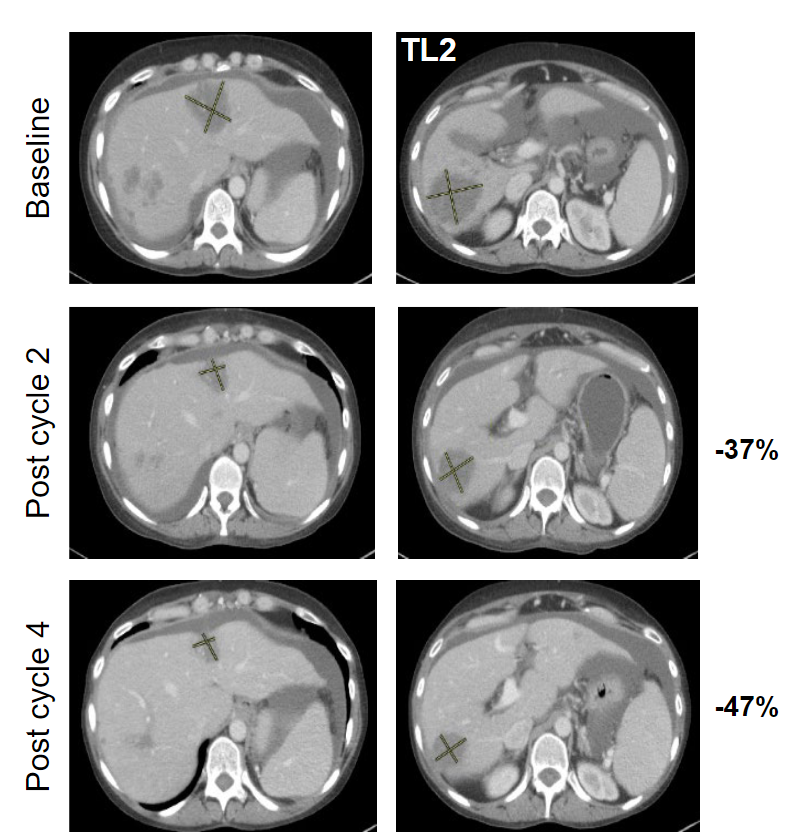

近50%患者肿瘤显著缩小​!结直肠癌患者迎来重磅新药​!

近50%患者肿瘤显著缩小​!结直肠癌患者迎来重磅新药​!发布时间:2022-12-29    作者:小编

结直肠癌患者有新药了!在最新公布的一项临床实验数据中,所有的28名结直肠癌患者在接受治疗后肿瘤控制稳定或显著缩小,疾病控制率高达100%!...